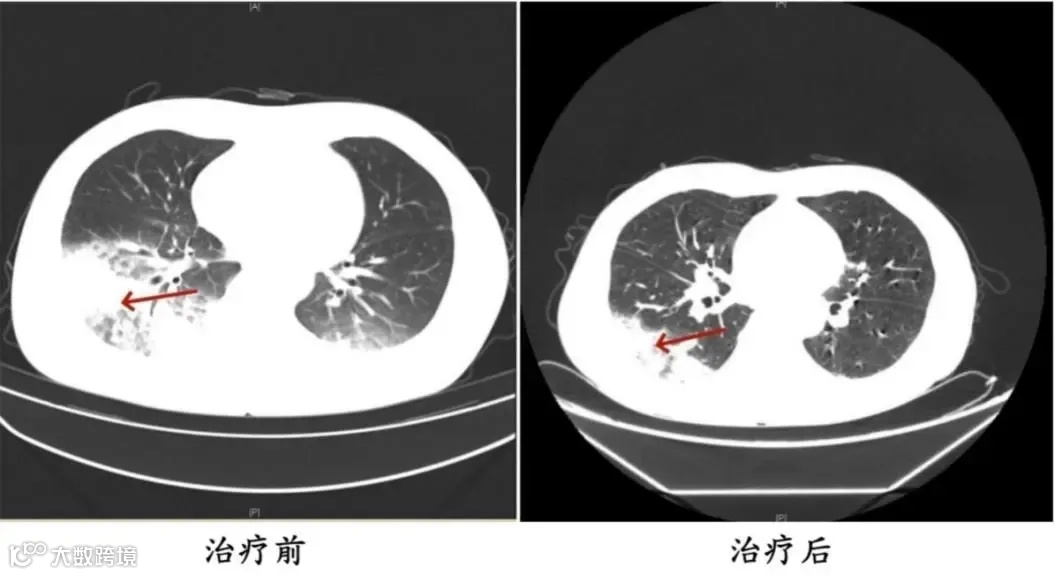

与周先生同一时间入院的还有32岁的宁乡市市民姚女士(化名)。据她介绍,家里的空调半年多没有清洗过了,入院前她在家用了两天空调,一周后相继出现了咳嗽、咳痰、高热、寒战、呕吐、腹泻等症状。在当地诊所被诊断为“急性胃肠炎”,经初步治疗未见效,病情加重转入长沙市中心医院呼吸与危重症医学科继续治疗。

姚女士患有2型糖尿病、甲状腺恶性肿瘤(乳头状癌术后)、甲状腺功能减退、特纳综合征等病史,是免疫力低下人群。医生结合体格检查及相关辅助检查结果,初步判断患者为重症社区获得性肺炎。经抗感染治疗后,患者的病情逐渐加重,反复高热,出现多脏器功能异常,如心肌酶谱异常升高、低钠血症、血尿、蛋白尿等状况。

医生通过分析患者咳出橘红色痰以及肺内、肺外表现,建议完善病原学检查,最终确诊为重症军团菌肺炎。调整用药后,患者病情迅速好转,体温逐渐恢复正常,各项指标也逐步恢复。